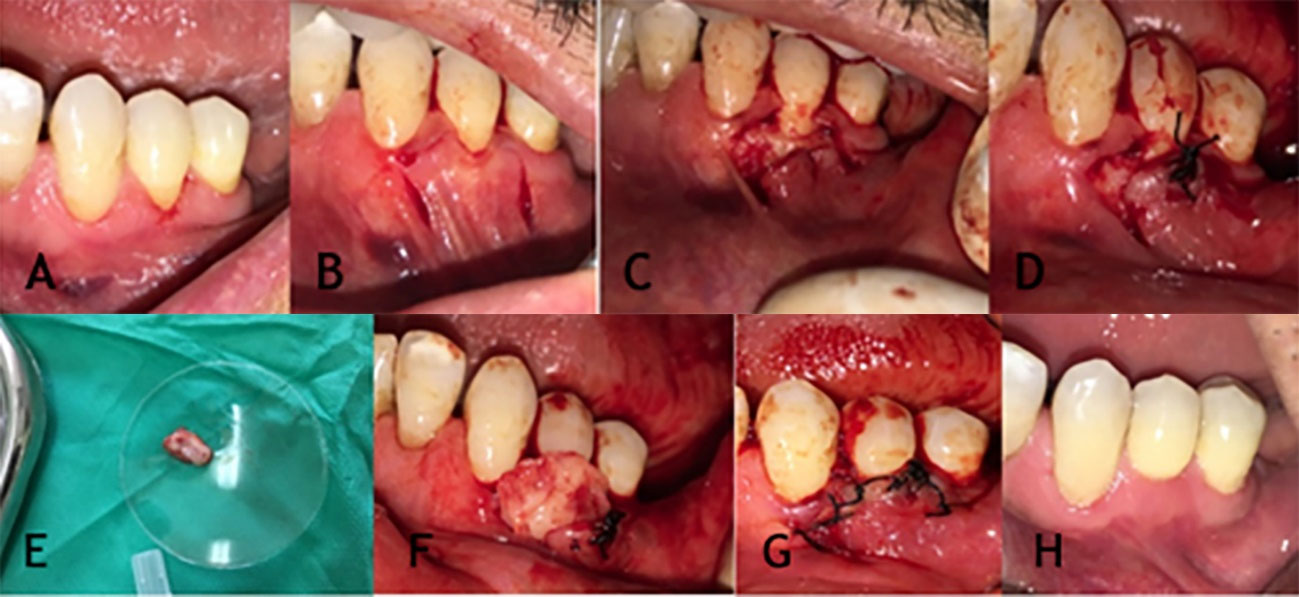

Any existing tissue tags were removed, and after placing the PRF membrane on the gingival area, the membrane was sutured with catgut suture, after which the acentric flap was closed with silk sutures (0-5). No membranes were used in the control group (Figure 1 A to H & Figure 2). All parameters were measured at first & third month after surgery.

Figure 1.

Steps of root coverage surgery using Acentric double pedicle graft with PRF.